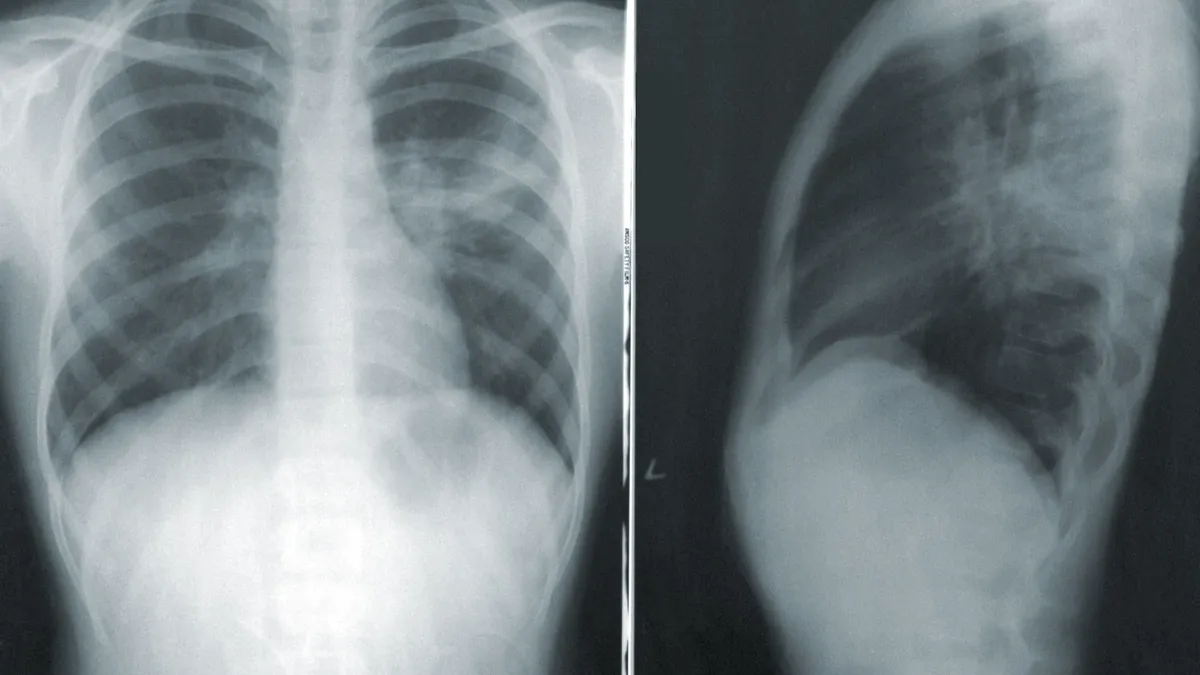

Кроме того, в 2021 году почти в три раза выше нормы оказалась заболеваемость пневмонией. Избыточно ей переболели 1,1 млн человек.

Год назад Роспотребнадзор открыто признавал, что в 2020 году «значительная часть не подтвержденных лабораторно заболеваний COVID-19 регистрировалась как ОРВИ и внебольничные пневмонии».